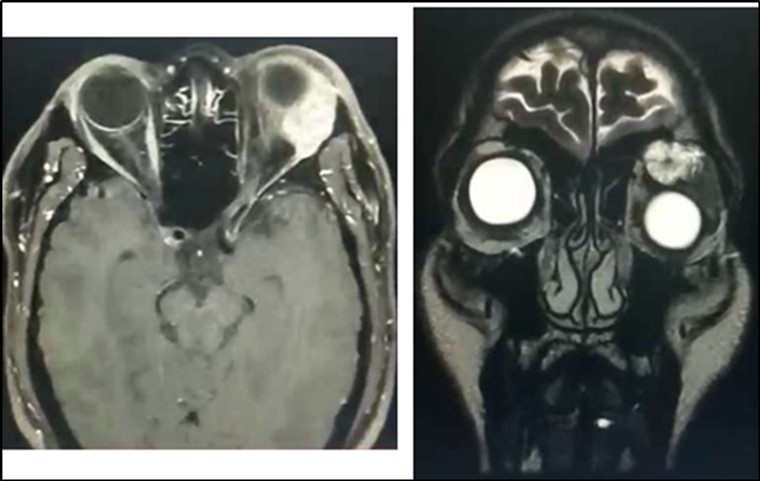

Orbital MRI showed a 2.6 x 2.9 x 3.2 cm (cc x w x ap) heterogeneously enhancing mass seen in the extraconal space (superolateral aspect) likely arising from the left lacrimal gland (Figure 2). The lesion exhibits mixed (predominantly hyperintense T2 wave and predominantly intermediate T1W) signals. Mass effect was noted compressing the retrobulbar fat with resultant medial displacement of the optic nerve, inferior displacement and anterior protrusion of the globe. The mass abuts the superior rectus, levator palpebrae superioris and lateral rectus muscle.

Figure 2.Orbital MRI showing an enhancing lacrimal gland mass (Axial & Coronal Views), left

Orbital MRI showing an enhancing lacrimal gland mass (Axial & Coronal Views), left